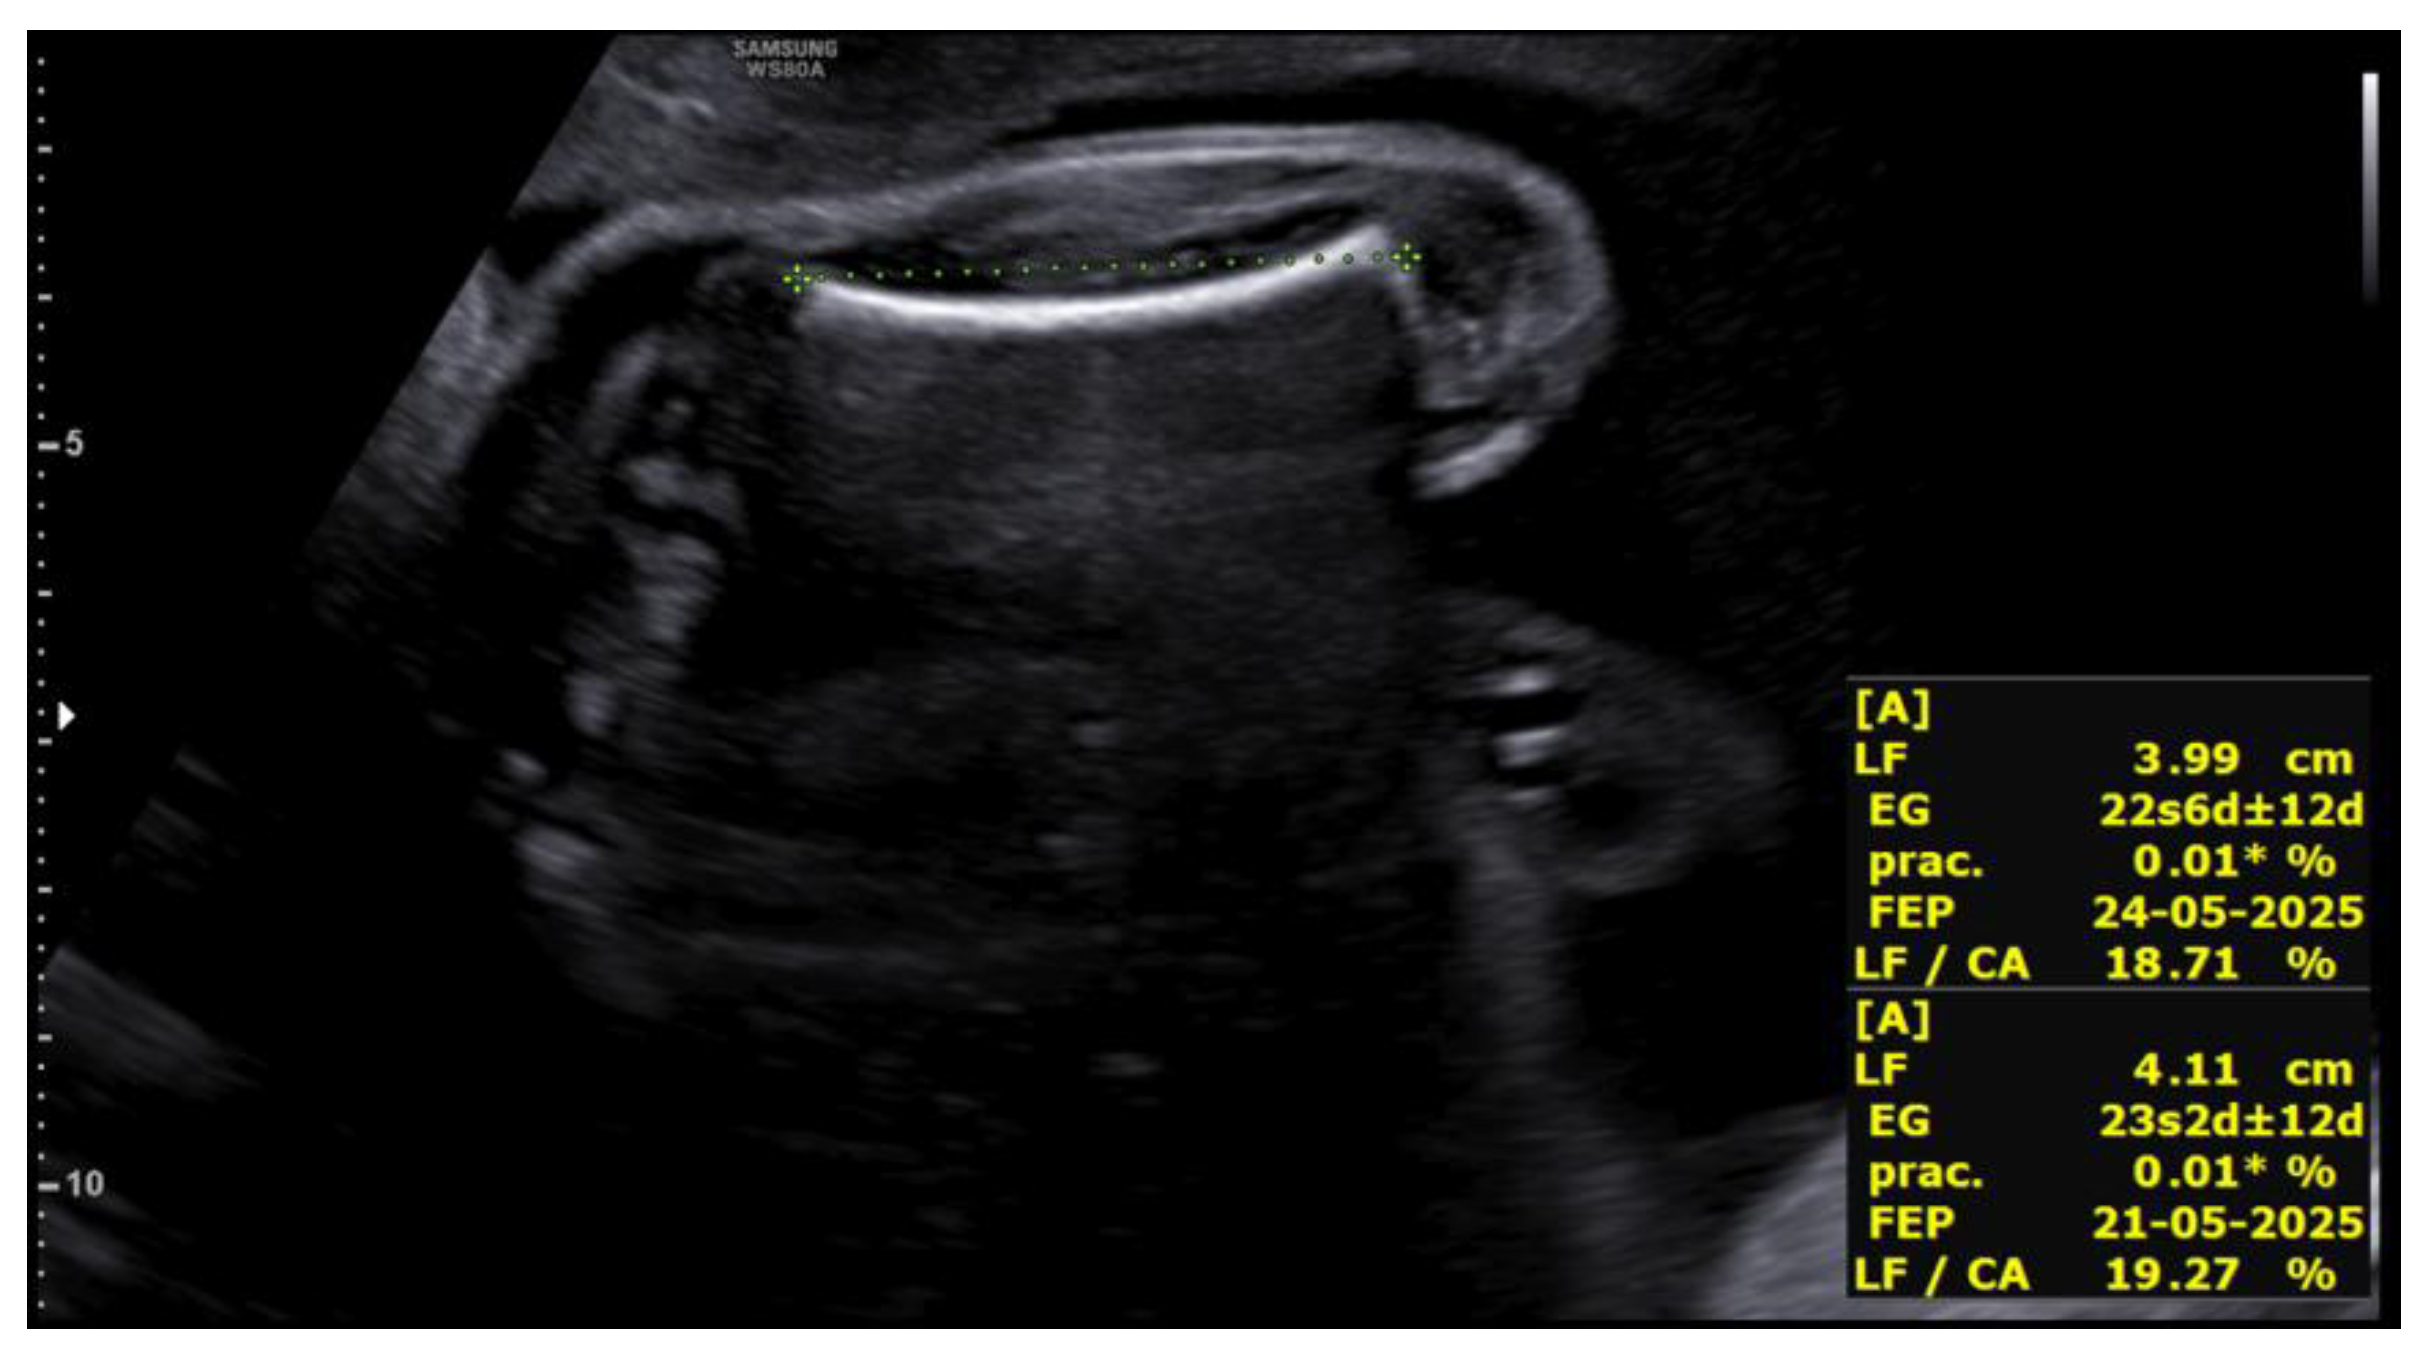

Figure 3. Cephalic index >85% (brachycephaly) in the first fetus at 23+5 weeks.